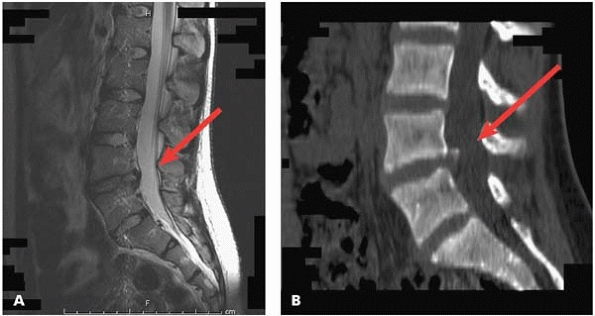

is an active attempt to heal the pars lesion (Fig. 20-5). Bone scan can also help to rule out other pathology. A CT scan with fine cuts may best define the lesion (Fig. 20-6). A CT scan can also be used to follow up healing after brace treatment, although this is not a routine for many orthopaedists.

▪ FIGURE 20-6

CT scan showing bilateral pars defects. There is significant sclerosis, and the edges of the defect appear rounded and remodeled. CT gives you and the patient much information not available with other imaging. In this case, it suggests that the lesion is chronic; many would say this is one that would be difficult to completely “heal.” |